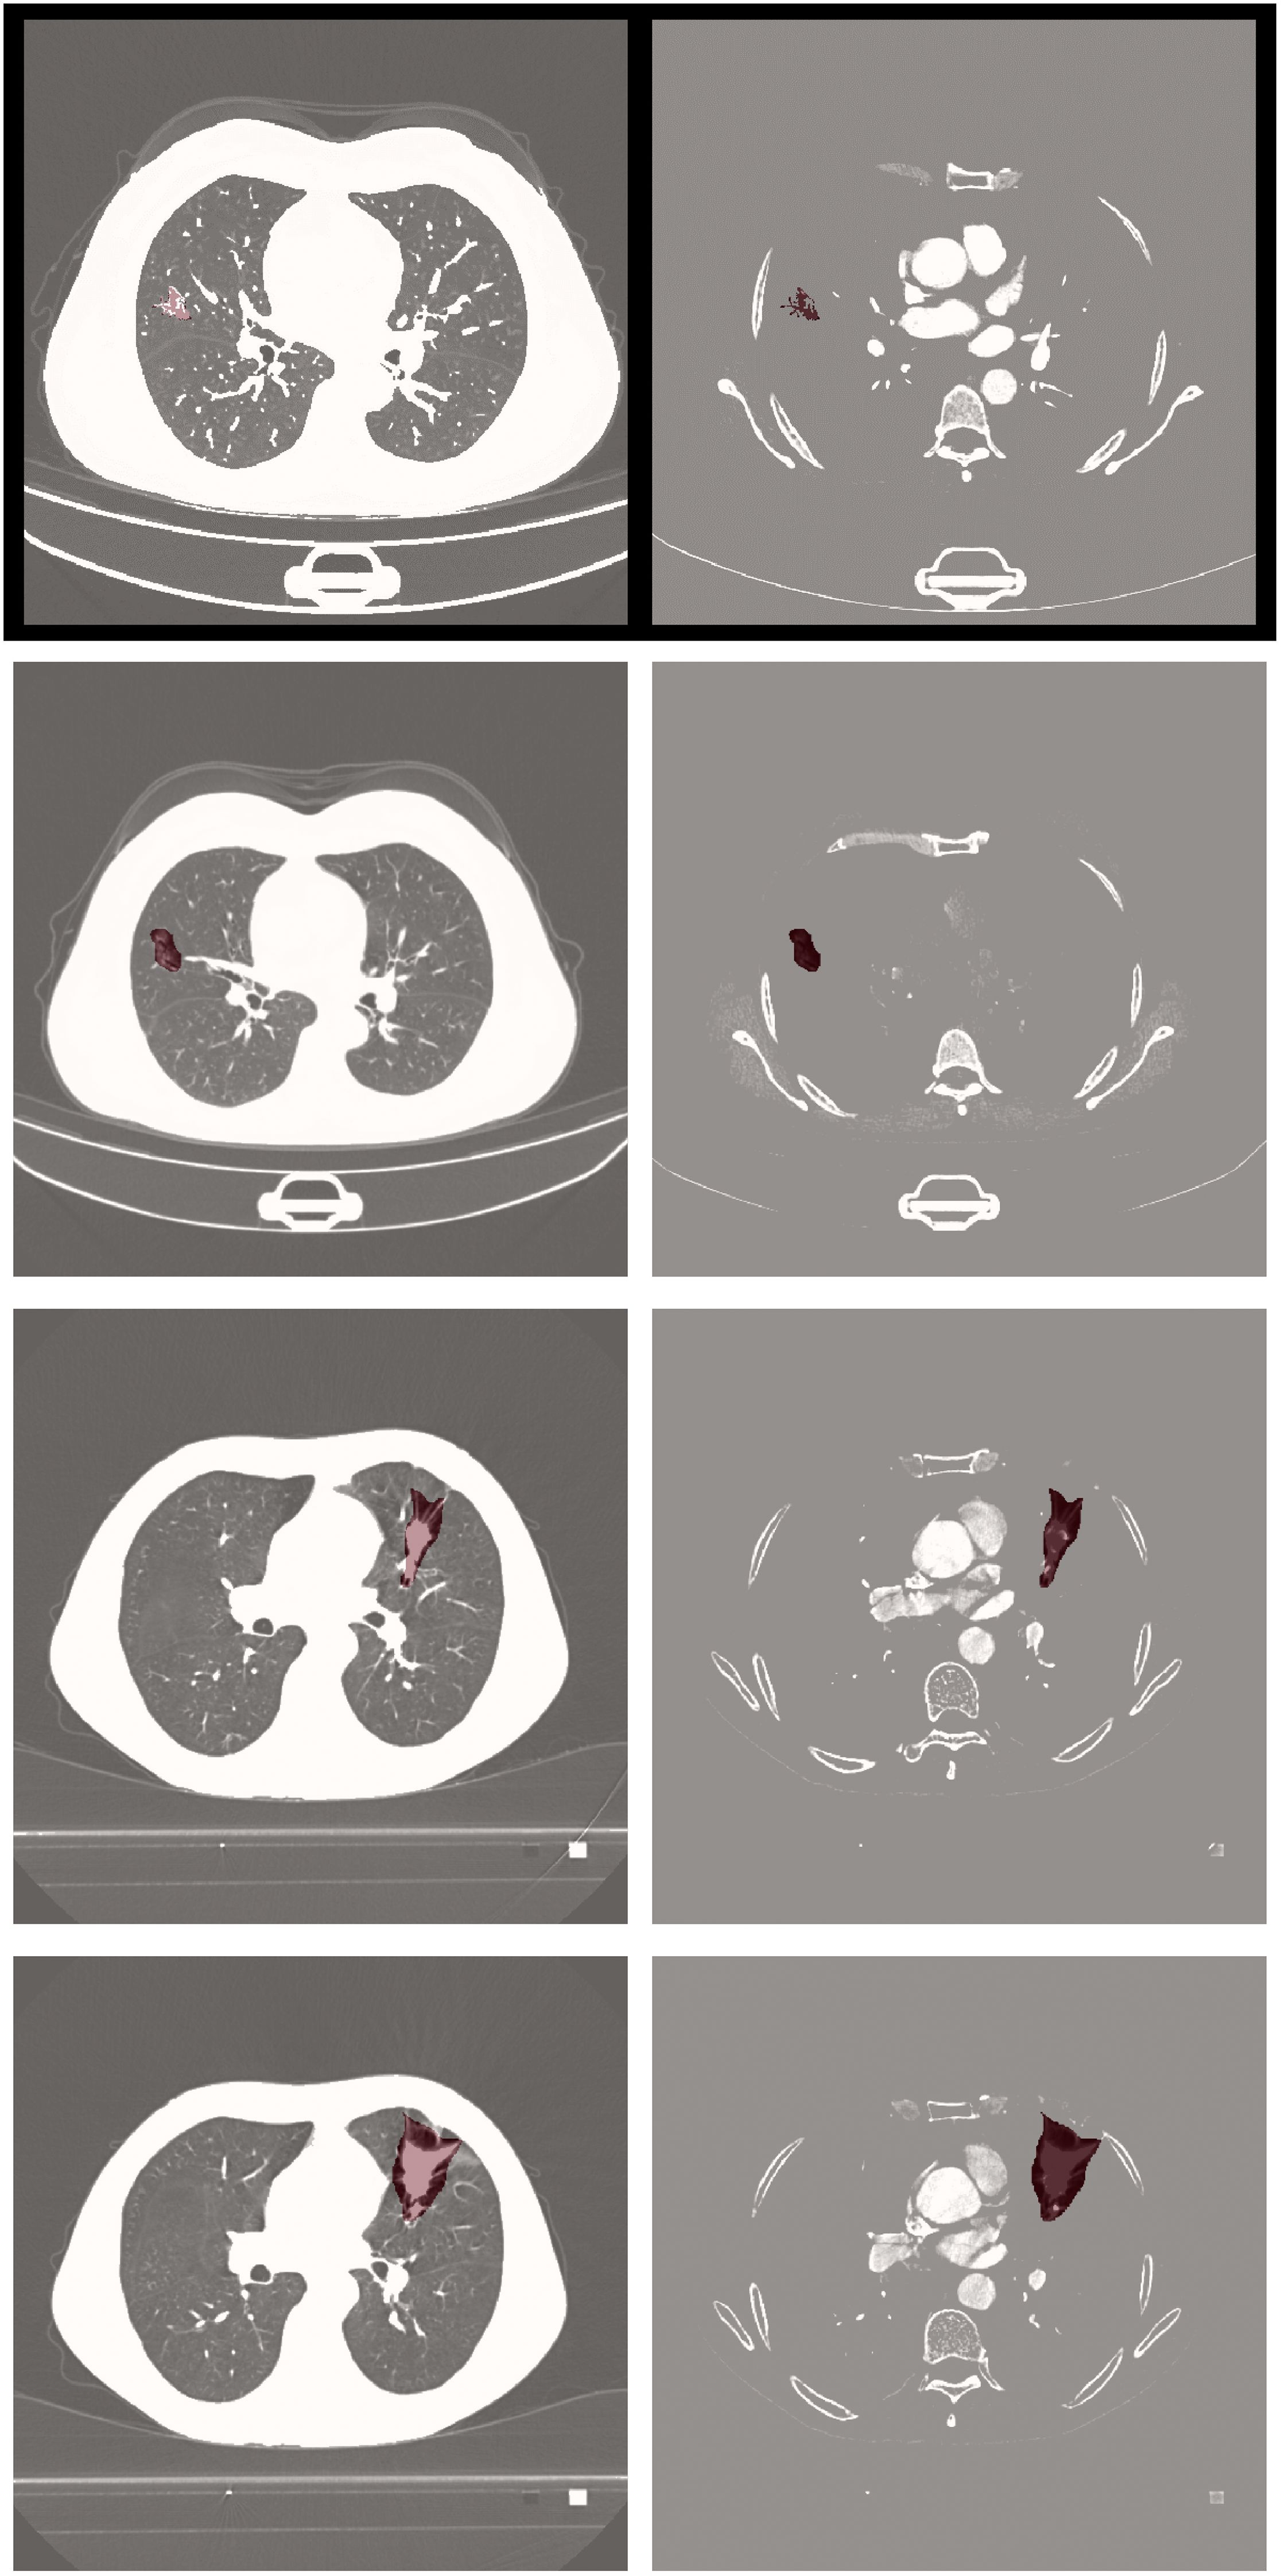

Visual comparisons of segmentation outcomes, as depicted in Figure 5, underscore the proficiency of MK-UNet in managing intricate tumor morphologies. Specifically, in instances of infiltrative adenocarcinoma characterized by irregular margins, the model successfully maintained fine structural details, such as pleural extensions, which were frequently oversmoothed by the 3D U-Net. In contrast, for benign nodules, MK-UNet adeptly excluded inflammatory regions that were misclassified as tumors by alternative models.

Figure 5

A series of CT scan images of lungs arranged in a grid, highlighting various regions in red within the lung fields. Each image shows different cross-sections, with red spots indicating abnormalities or areas of interest. The scans show varying densities, with the lungs appearing in grayscale against a black background.

Figure 5. From left to right: input image, predicted output (tumor segmentation location), and ground truth (manual labeling). The input CT slice (left) includes the entire lung field, but the model only processes the cropped tumor region (delineated by the red box in the input image) for segmentation.